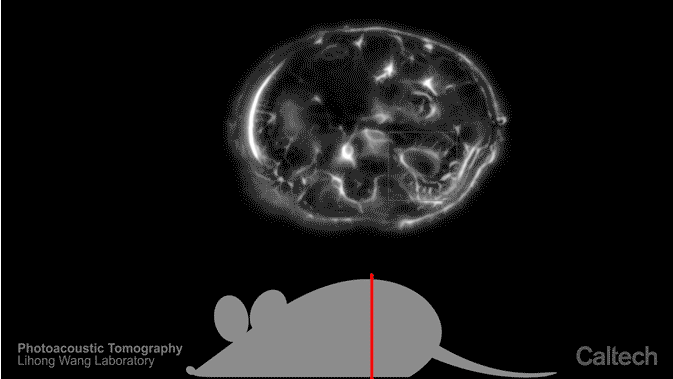

图为用光声成像技术生成的小鼠器官图像。该技术将光线与超声波结合,可实时生成完整的断层扫描图。

此次研究由杜克大学和加州理工学院联合开展。该技术名为“单脉冲光声计算机断层扫描成像”(简称 SIP-PACT),利用光显微技术和超声波成像技术观察动物的体内状况。研究人员称,对小型动物的活体扫描一直存在图像分辨率和扫描速度的限制,而这一新技术可以解决这一问题。

它可以实时生成动物体内的断层扫描图,以成年小鼠为例,每秒可生成 50 张完整的断层扫描结果。“光声成像技术可以实时生成小型动物身体的完整断层扫描图像,被我们寄予厚望。”此次研究的共同作者、杜克大学生物医学工程助理教授 Junjie Yao 博士指出,“利用这一技术,研究人员可轻松监测药物在动物体内的分布情况,以及不同器官对药物的反应。”

核磁共振成像技术(MRI)也能观察到组织内部情况,但需要借助强大的磁场,且生成图像的时间较长,从几秒到几分钟不等,X 光和正电子发射计算机断层扫描技术(PET)又会产生大量辐射,不可用于长时间观察,但光声成像技术利用的是强大而短暂的激光脉冲,可在保证安全的前提下、使细胞发出超声波,进而穿透身体组织。 在此次最新研究中,Yao 博士和加州理工学院的 Lihong Wang 博士还使光声成像技术的速度和扫描范围都得到大幅提升。他们组建了一台环形超声探测器和一套快速数据采集系统,利用三角测量法确定小型动物体内各道超声波的来源,最终,改进后的成像技术可深入生物组织内部五厘米,分辨率达亚毫米级,同时还保留了传统光显微技术提供的信息。